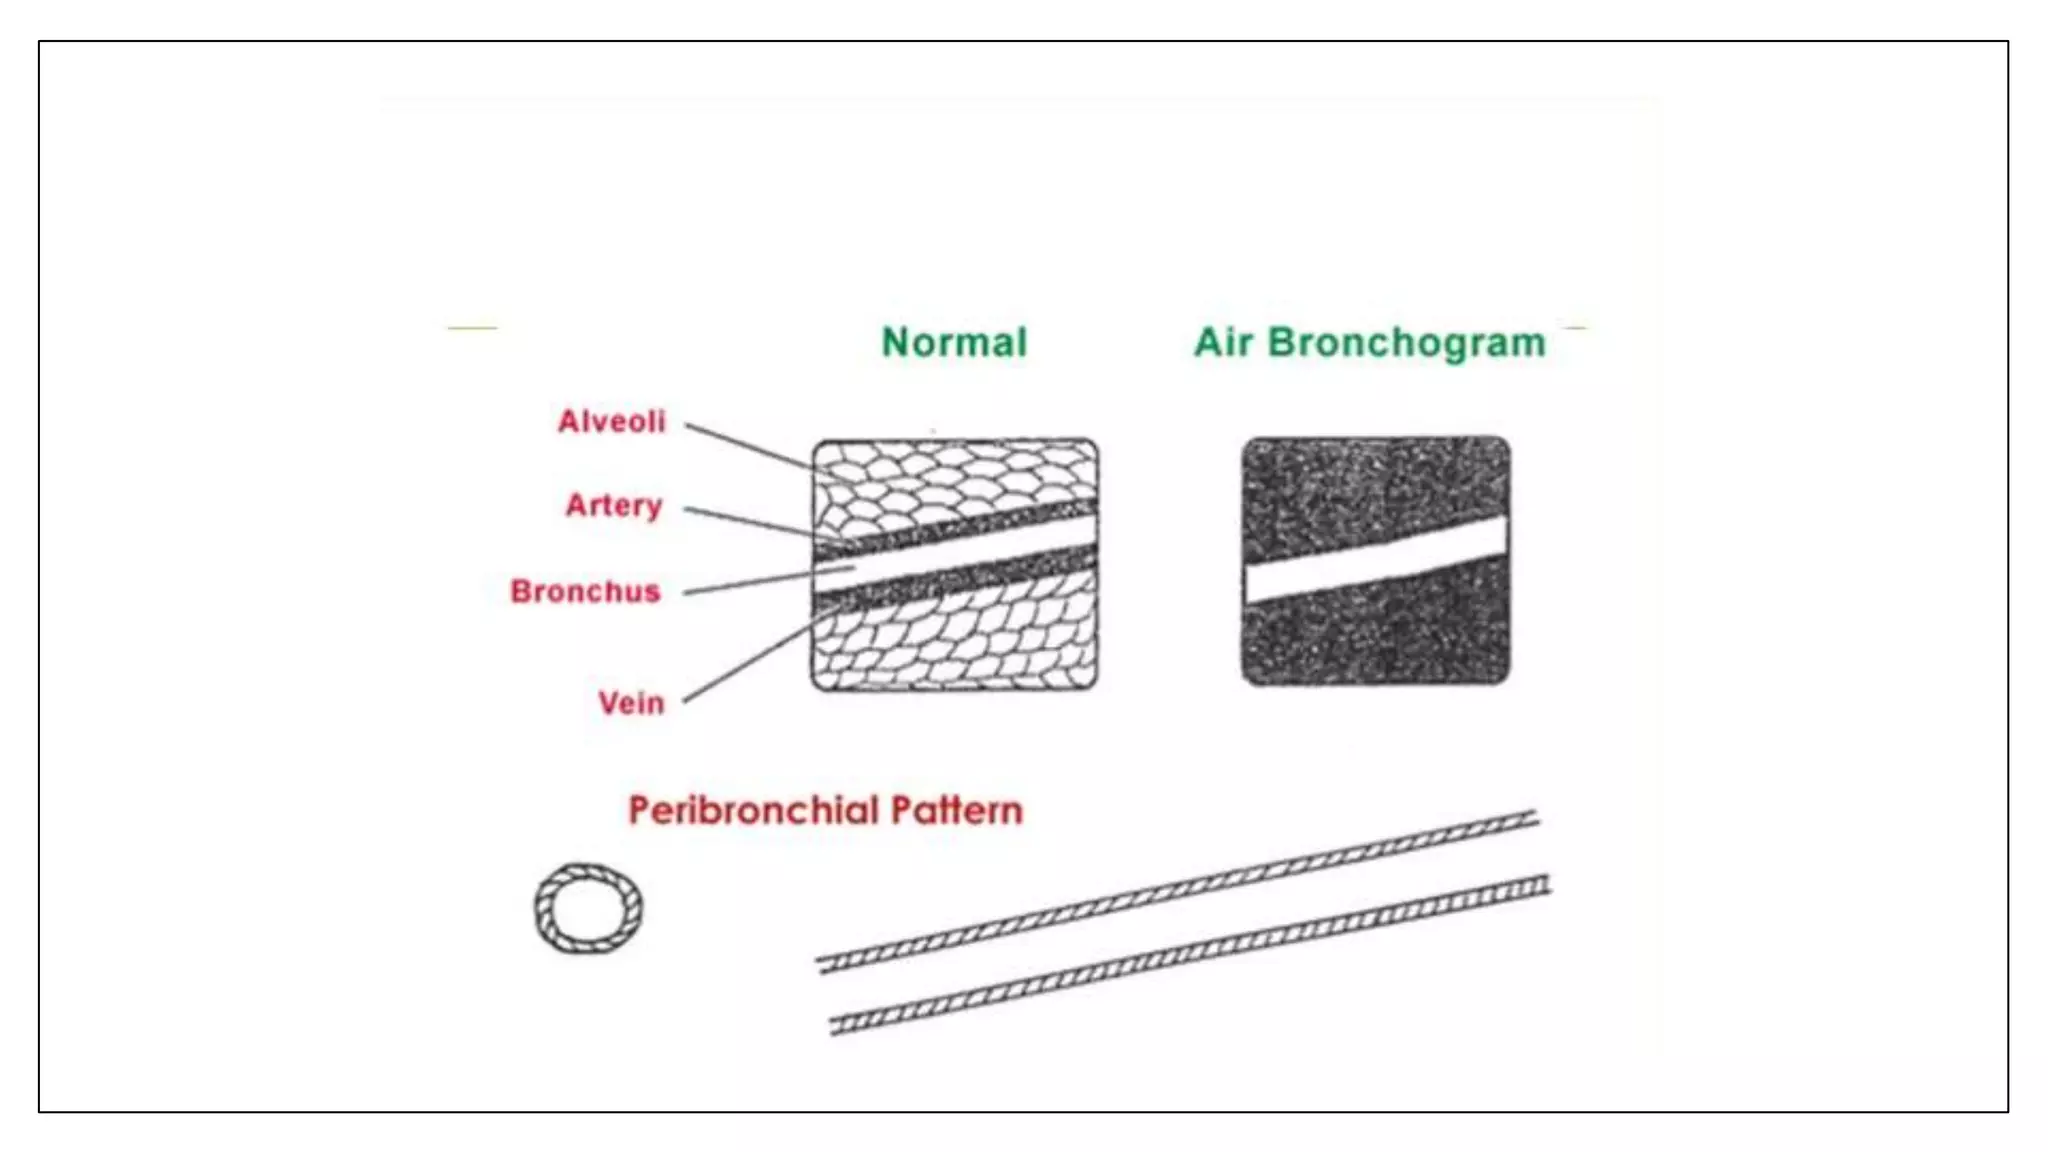

The document provides guidance on approaching and interpreting chest x-rays (CXR). It outlines steps to check the name, date and quality of the film, systematically scan the CXR looking for abnormalities, and determine if the lungs appear too white or black. Specific signs are described to help localize abnormalities, including the cardiac silhouette sign and pleural effusion signs. Examples are given of respiratory distress syndrome, tetralogy of fallot, transposition of great arteries, and total anomalous pulmonary venous return. The take home message is to summarize positive findings, compare to prior CXRs if available, and confirm findings with a radiologist.